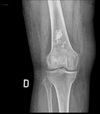

83

80 year old female with pain and swelling in the right knee. What is on your list of differential diagnoses in order from most to least common?

Stippled calcification = ICE 1. Chondrosarcoma 2. Infarct (Serpiginous) 3. Enchondroma

84

Give a list of differentials in order from most to least likely.

1. Chondrosarcoma (large calcified soft tissue mass) 2. Enchondroma 3. Infarct